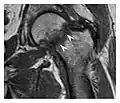

The greater tuberosity of the humerus is also an illustrative location of occult fractures. The osseous injury may follow seizures, glenohumeral dislocation, forced abduction, or direct impaction. They are commonly discovered on MRI in symptomatic patients with suspicion of rotator cuff tear. Coronal images are best suited for detection. They appear as crescentic oblique lines surrounded by a bone marrow edema pattern (Figure 5). The rotator cuff must be inspected since associated ligamentous lesions are common. In the ankle, malleoli and tarsal bones should be checked carefully for any cortical disruptions and radiolucent lines that may reveal a fracture. Awareness of the exact location of the pain will help direct the attention of the interpreter when searching for very subtle signs of fracture (Figure 6).[1]

Figure 6: Subtle anterior talar fracture in a 39-year-old man presenting with ankle pain after a fall. (a) Anteroposterior radiograph shows a subtle oblique radiolucent line through the talus (white arrows). (b) Sagittal CT reformation confirms the presence of an anterior talar fracture with cortical offset (black arrow). Avulsion fractures, which consist of a detached bone fragment resulting from a ligament or tendon pulling away from the bone, may also present with subtle radiographic signs. Tiny osseous fragments near the presumed attachment site of a ligament suggest this diagnosis. Common sites are the lateral tibial plateau (the Segond fracture), the spinal tuberosity of the tibia resulting from anterior cruciate ligament avulsion, and the ischial tuberosity.[1]

Figure 7: Fatigue fracture of the talus in a 25-year-old male basketball player with right hind foot and ankle pain, without history of trauma, and a normal initial radiograph (not shown). (a) One-month followup lateral radiograph shows normal appearance. (b) Sagittal T1-weighted MRI shows an irregular fracture line (arrow) within an ill-defined area of hypointensity corresponding to bone marrow edema.[1]